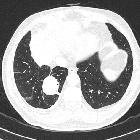

asbestos-related lung and pleural diseases as an endemic exposure in Egypt. A 56-year-old male smoker patient, working in plasters for 13 years, was diagnosed as having round atelectasis for 3 years with a latent period 10 years. Axial CT scan lung window showing left lower lobe subpleural soft tissue density with comet tail sign and underlying pleural thickening denoting round atelectasis

Round